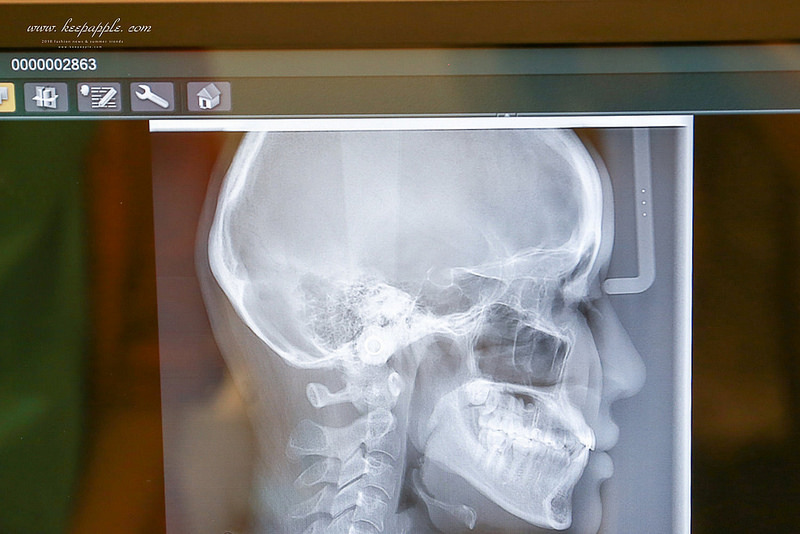

「X光室」使用的是近幾個月出的 Veraview X800 斷層掃描儀

這可是全台第一、二家進的機器

在台灣只有兩家有 (另一台在台北)

精準度比一般的還高

我覺得這超厲害的!!!

這次是要來做隱適美的事前功課

諮詢之前會先到X光室拍攝

再和醫師討論之後需要的療程

運用最新尖端的設備

能更精準地了解客人想改善的地方